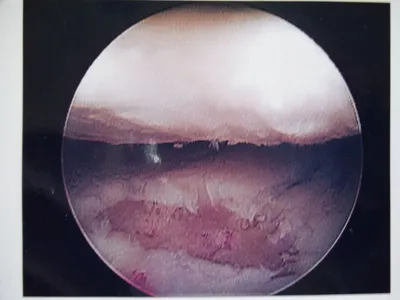

A series of intraop ankle arthroscopy pics of synovial chondromatosis with OCD talus and tibia and microfracture.

Pic of one of the nodules inside the ankle joint.